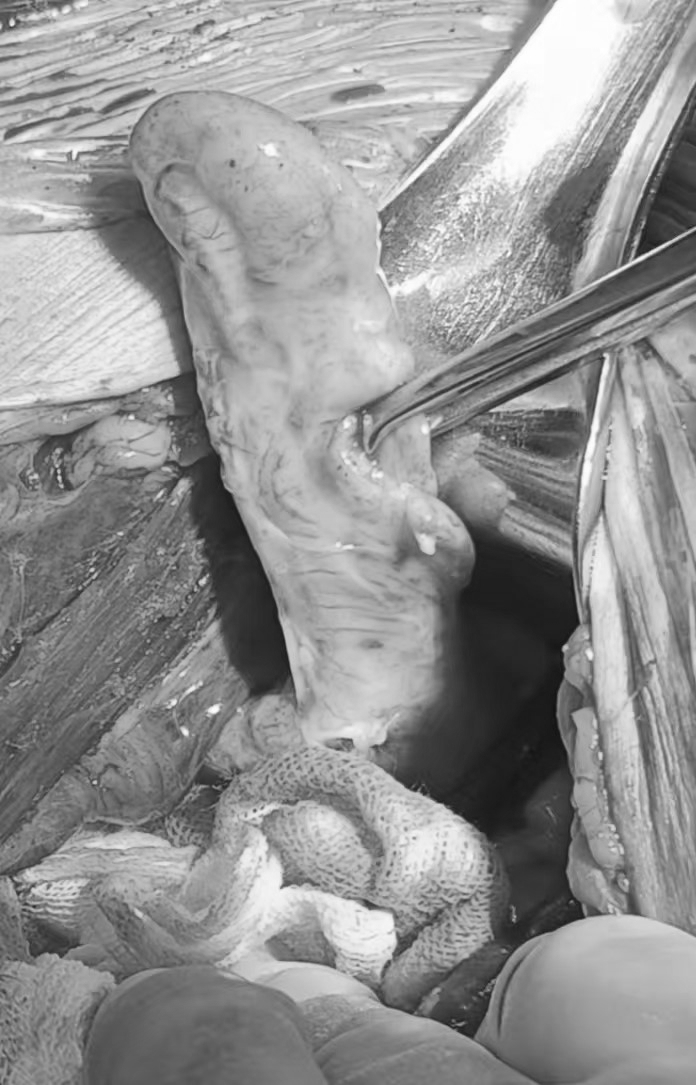

结局:急诊手术,剖宫产手术顺利娩出一女活婴,评分良好。术中请普外科医师同台探查见阑尾增粗、充血水肿,表面覆有脓苔,术中诊断:急性化脓性阑尾炎。遂决定行阑尾切除术(过程顺利)。术后积极给予抗感染治疗。术后6天正常出院。出院2周复查未提示明显异常。